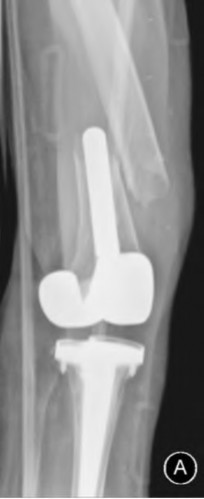

During a complex revision TKA, the surgeon notes profound laxity and attenuation of the medial collateral ligament (MCL) such that the knee cannot be balanced coronally in either flexion or extension. The extensor mechanism and posterior capsule remain completely intact. Which level of prosthetic constraint is most appropriate in this scenario?